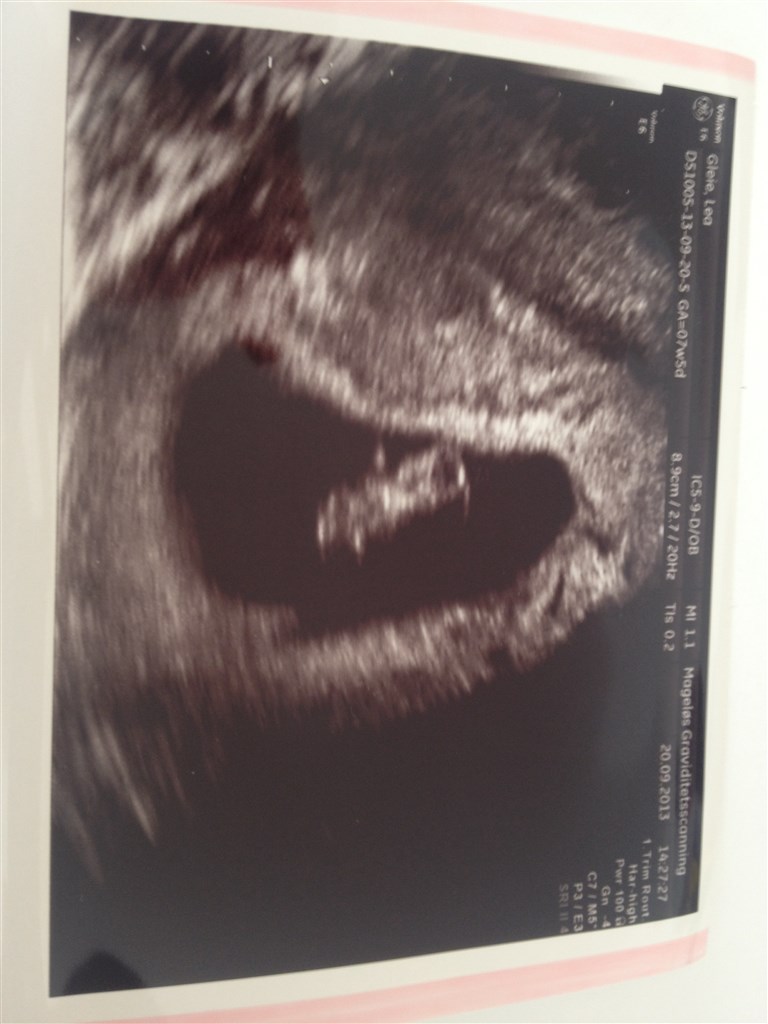

Juhuu. Så var det igår min tur til at blive scannet tidligt. Og ALT var som det skulle være! Det var virkelig stort.

den scanning har virkelig hjulpet mig til bedre at kunne tro at jeg ER gravid!!

Babyen var 14,5mm så jeg er sat to dage længere frem, med termin d. 4. Maj (på farfars fødselsdag).

Sikke en skøn oplevelse.